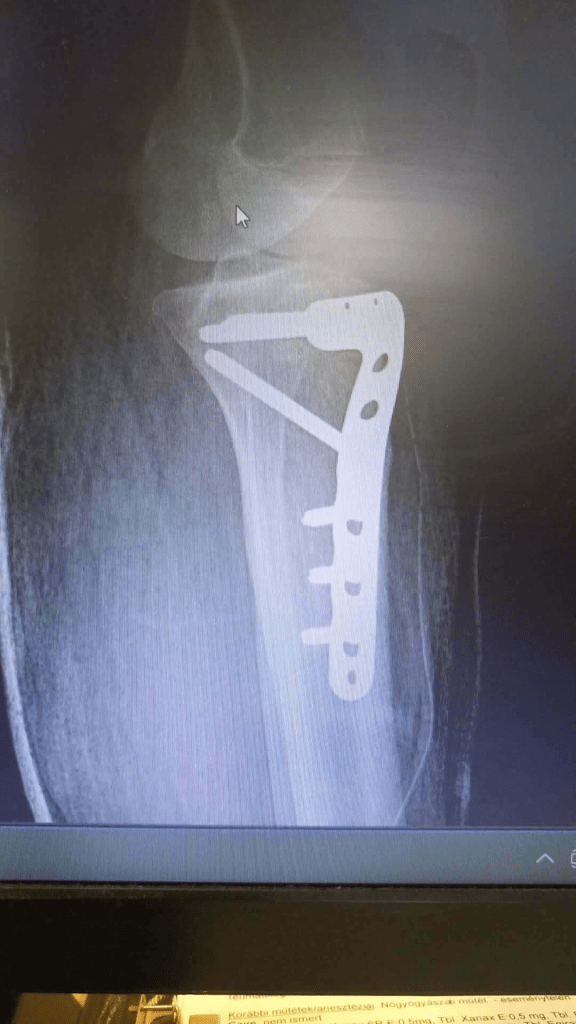

műtét.

A térdem?

Nem fáj.